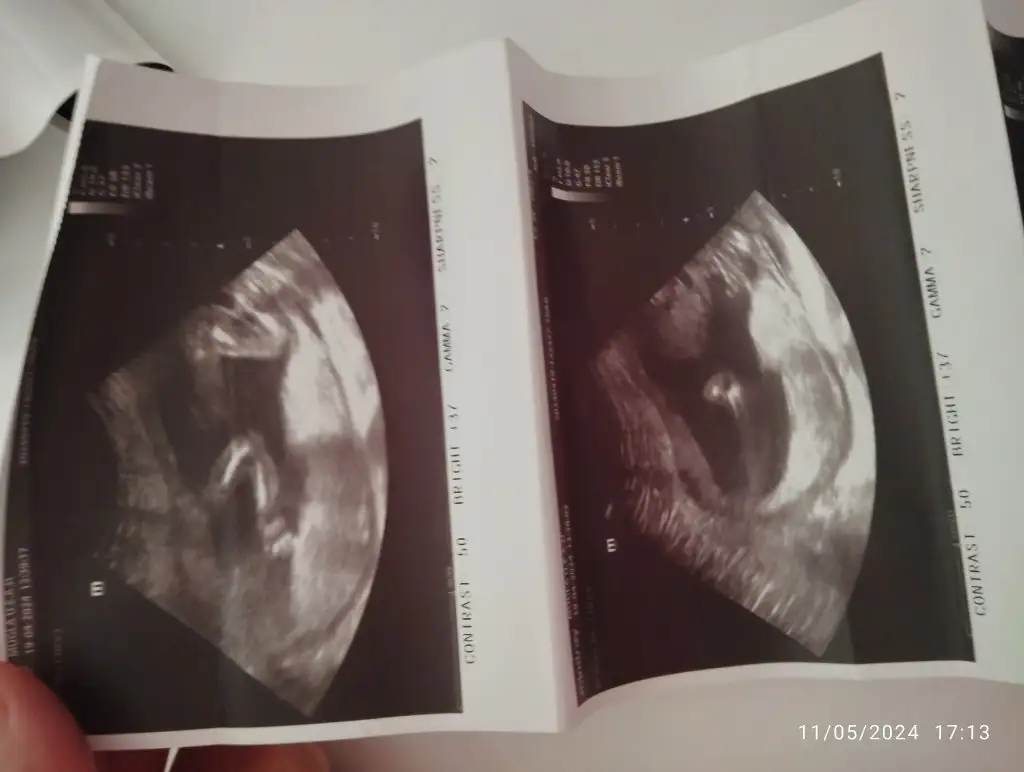

12+6 ydı bir hafta geç döllenme aslında 13+5 olması lazımdı 😂 karından ultrason